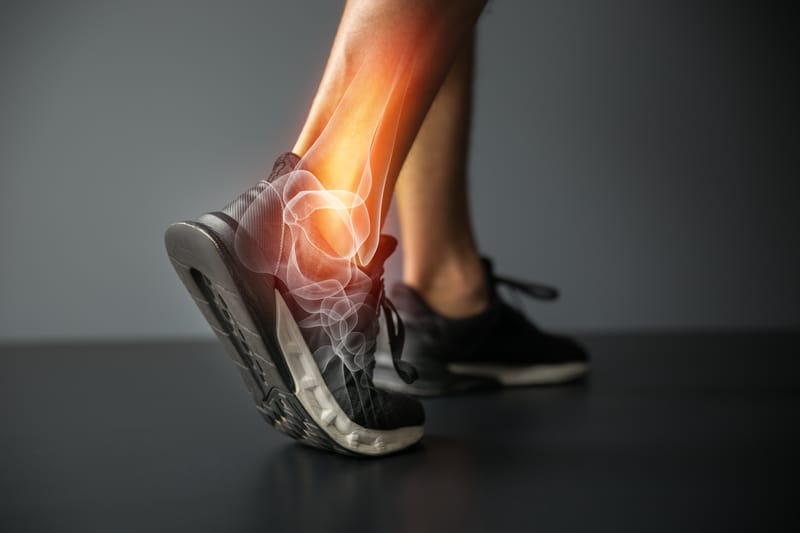

Providing care for sport ankle injuries

Corrective osteotomies, tendon transfers, fusions